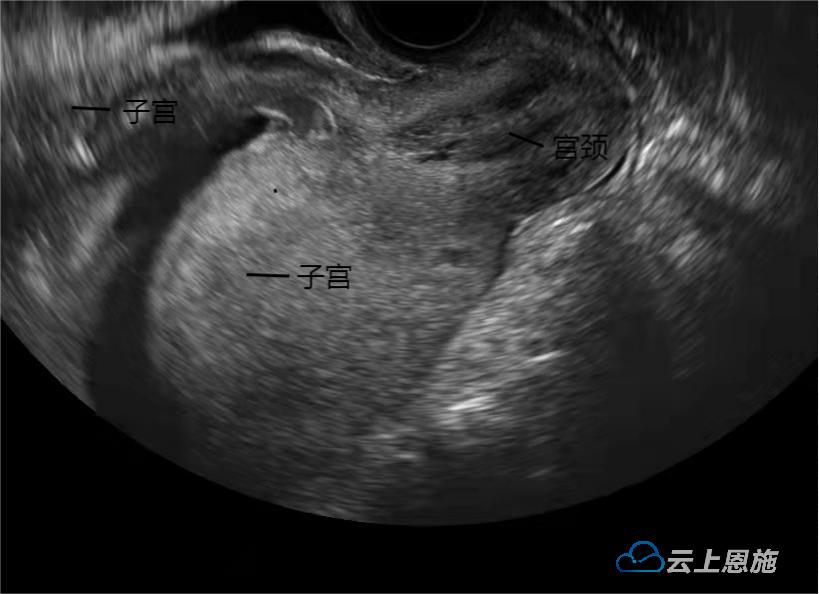

图2 治疗前

尽管病因非常少见且病情凶险,但在副主任医师苏瑞芬带领下,妇儿医院产科团队反复查阅文献资料,反复讨论,为患者制订诊疗方案。通过超声引导下经阴道手法上推受压翻转子宫复位,并给予持续导尿、胸膝卧位等对症处理后,7月25日复查显示,游女士子宫位置恢复正常(图3)并于当天拔除尿管,小便恢复正常,无流产征兆。7月27日,游女士顺利出院。目前经电话回访得知,游女士排尿正常,没有任何不适,母子平安。